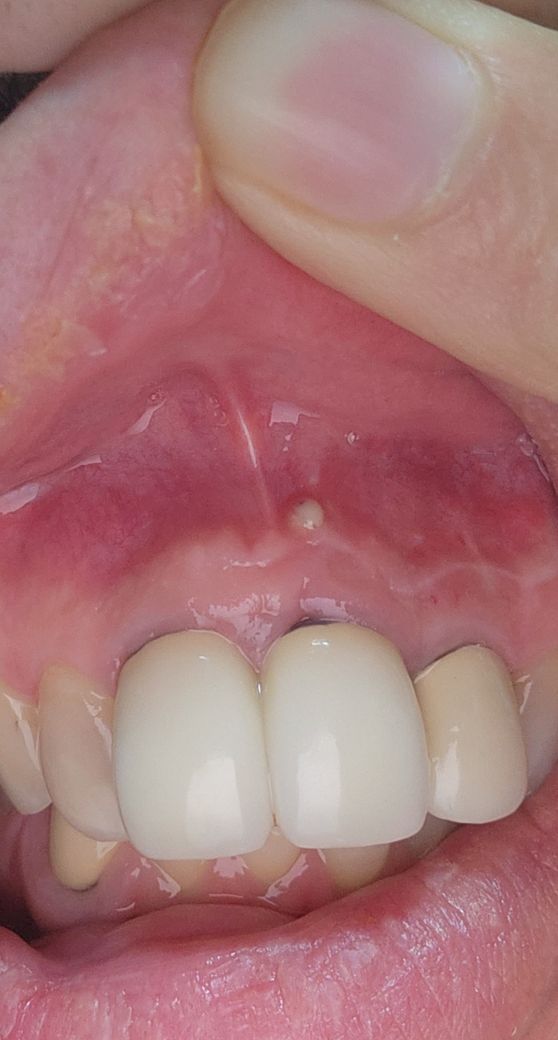

치과 잇몸 마취후 이런게 생겼는데 무엇일까요~?

치과 잇몸 마취후 사진에서 보이듯 이런게 생겼는데 무엇일까요~???????????

잇몸에 염증이 있는 것으로 보이며 마취와는 관계없이 치아나 잇몸에 문제로 염증이 있는 것 같습니다.

저부분은 마취때문에 생긴게 아니라 치아 뿌리끝에서 염증이 생겨서 나오는 염증인거 같습니다. 재신경치료 또는 신경치료를 하셔야될수도 잇을것같습니다.

사진상으로는 잇몸 염증이 있어서 농이 잡힌 것으로 보입니다. 마취와 관련성이 있을 가능성은 높지 않고 원래 잇몸 내지는 치아 속 신경에 염증이 있어 그 염증이 잇몸의 가장 약한 부위 (지금 해당 부위) 로 빠져나와 농 주머니를 형성한 것 같습니다.

사진으로 봤을 경우에는 잇몸 위쪽에 물집 같은 것이 잡힌 것으로 보입니다 이런 물집은 보통 씨앗뿌리의 염증이 있는 경우에 생기는 경우가 많은데 치약 우리의 감염이 되면 그 감염 물질이 잇몸뼈를 뚫고 나와서 사진과 같이 부어오르게 됩니다.

없애기 위해서는 원인 자체를 없애야 하는데 치아 안쪽 신경에 감염이 원인인 경우가 많기 때문에 신경치료가 필요할 수 있습니다 자세한 확인을 위해서 치과에서 진료를 받아 보세요

농 주머니(sinus tract)가 생겼네요.

그런데 아마 마취 때문에 생긴게 아니고.

기존의에 있었던 농이 마취바늘을 통해 배출 통로가 생겨 흘러 나오는 것을 확률이 높습니다.